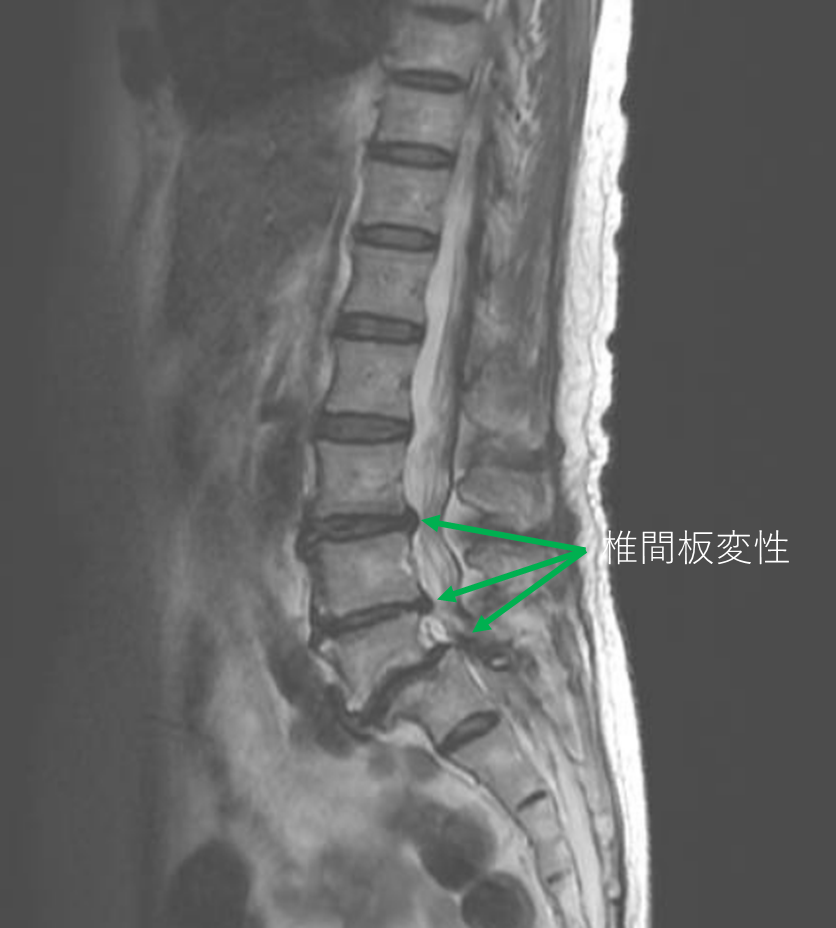

画像及び所見について

- L3/4,4/5,5/s-椎間板変性

以上の事が画像上認められます。

・L3/4,4/5-椎間板変性によって、主症状の原因の可能性がある。